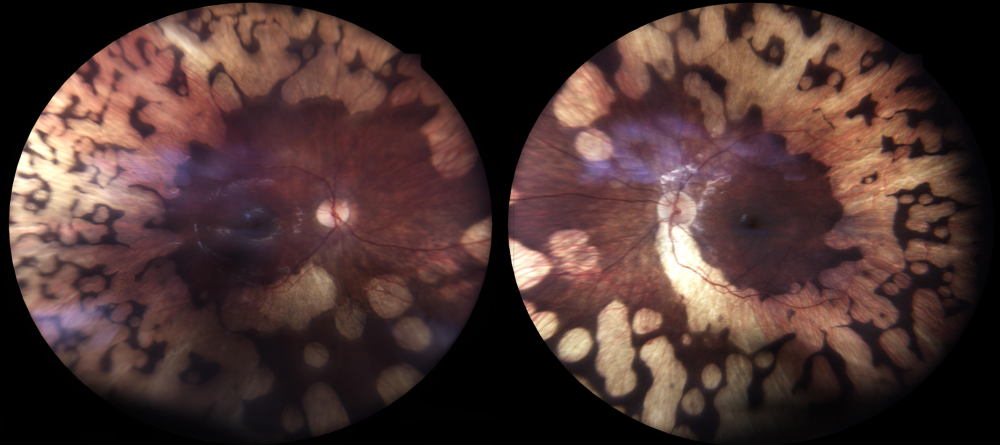

Título: When the Retina Mirrors the Moon

Descrição: Ultra-wide-field fundus autofluorescence (UWF-FAF) imaging showing an atypical retinitis pigmentosa (RP) phenotype in a patient with a CNGB1 variant.